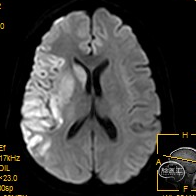

术后24小时复查颅脑MR未见明显出血。